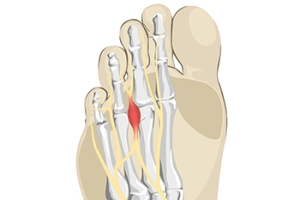

Plantar Fasciitis Causes Heel Pain

One of the most common causes of heel pain is the foot condition that is known as plantar fasciitis. The plantar fascia is a portion of tissue that is found on the sole of the foot. It connects the heel to the toes, and it may become inflamed or torn for various reasons. These can include obesity, standing on hard surfaces for most of the day, or wearing shoes that do not fit correctly. Patients have found the pain may be worse in the morning upon arising, and may feel better as the day progresses. This may be a result of moving the foot, and it is beneficial that specific stretches are performed during the day for continued relief. Additionally, wearing custom-made orthotics may help to reduce existing inflammation and increase comfort level. If you have heel pain, it is suggested that you are under the care of a podiatrist who can effectively diagnose and treat plantar fasciitis.

What Is Plantar Fasciitis?

Plantar fasciitis is one of the most common causes of heel pain. The plantar fascia is a ligament that connects your heel to the front of your foot. When this ligament becomes inflamed, plantar fasciitis is the result. If you have plantar fasciitis you will have a stabbing pain that usually occurs with your first steps in the morning. As the day progresses and you walk around more, this pain will start to disappear, but it will return after long periods of standing or sitting.

Plantar Fasciitis

Plantar fasciitis is one of the most common causes of heel pain. The plantar fascia is the thick band of tissue that connects the heel bone to the toes. When this band of connective tissue becomes inflamed, plantar fasciitis occurs. Fortunately, this condition is treatable.

People with plantar fasciitis often experience a stabbing pain in the heel area. This pain is usually at its worst in the morning, but can also be triggered by periods of standing or sitting. Plantar fasciitis may make it hard to run and walk. It may also make the foot feel stiff and sensitive, which consequently makes walking barefoot difficult.